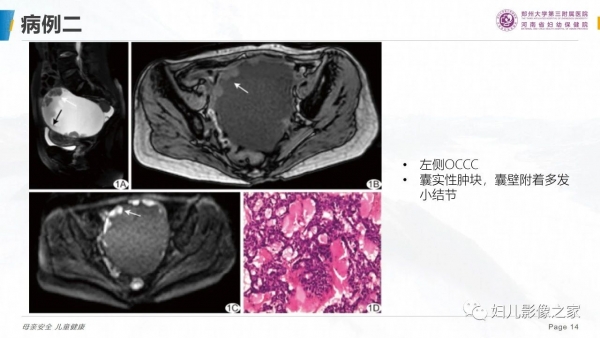

卵巢透明细胞癌

病史:患者女,57岁

主诉:尿频2月余,发现盆腔囊肿4天

现病史:2月前出现尿频尿急,4天前于当地医院彩超发现盆腔囊肿,无女性生殖器官出血,无腹痛

专科检查:于耻骨联合上方可触及拳头大小肿物